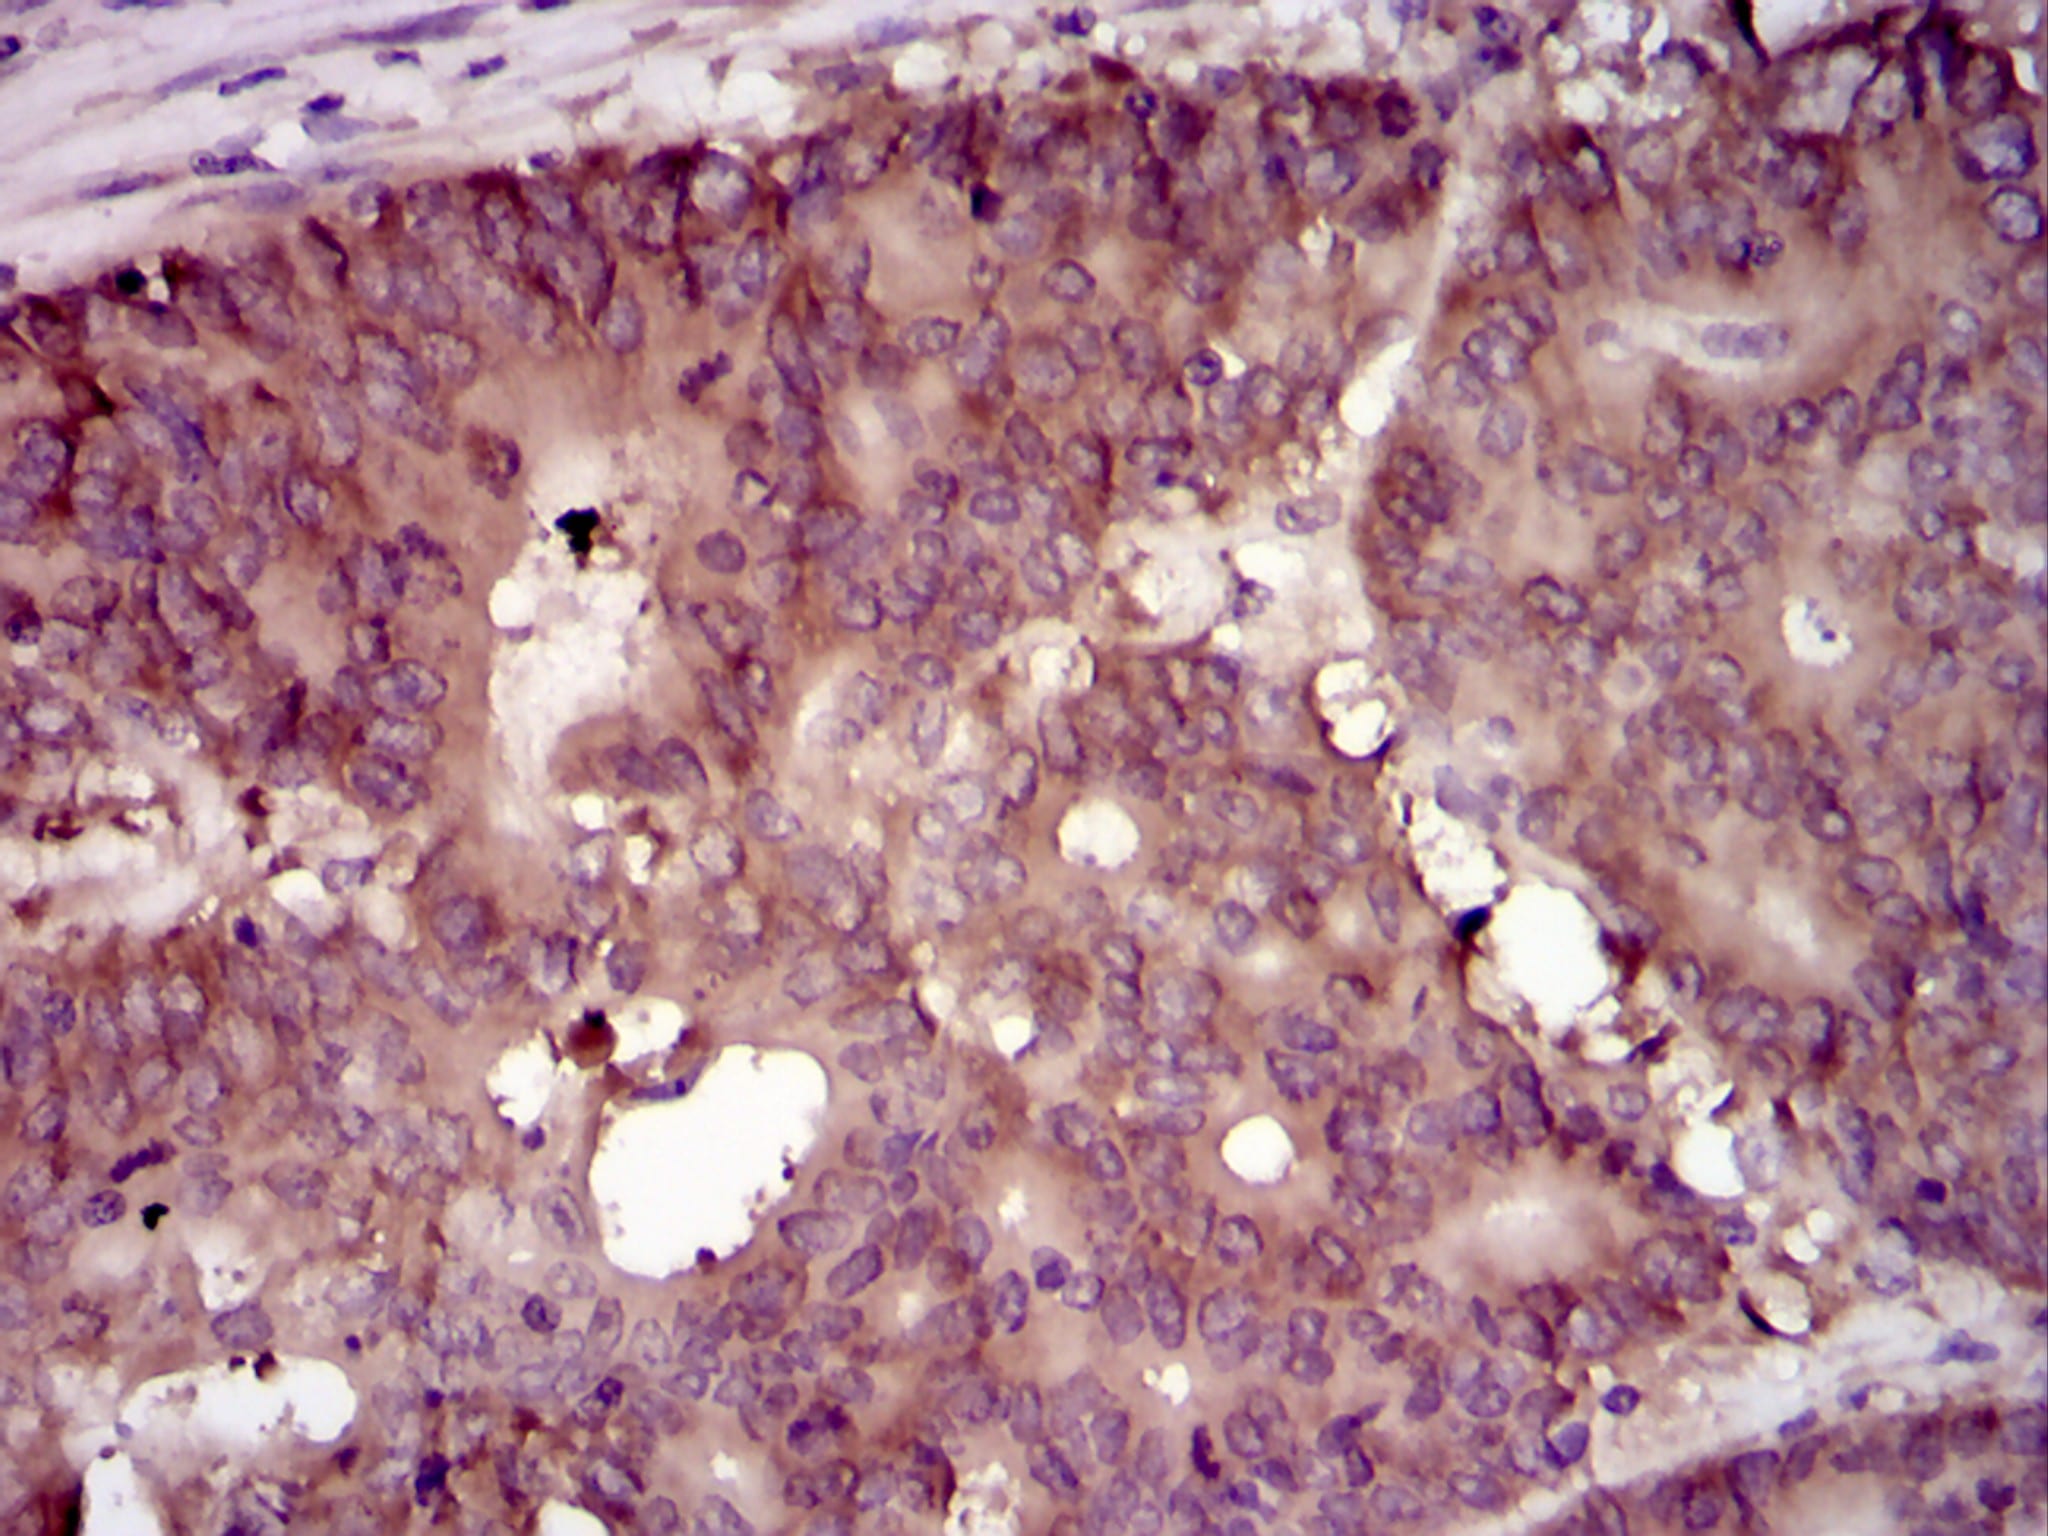

Immunohistochemical analysis of paraffin-embedded human colon cancer tissues using EIF4B mouse mAb with DAB staining.